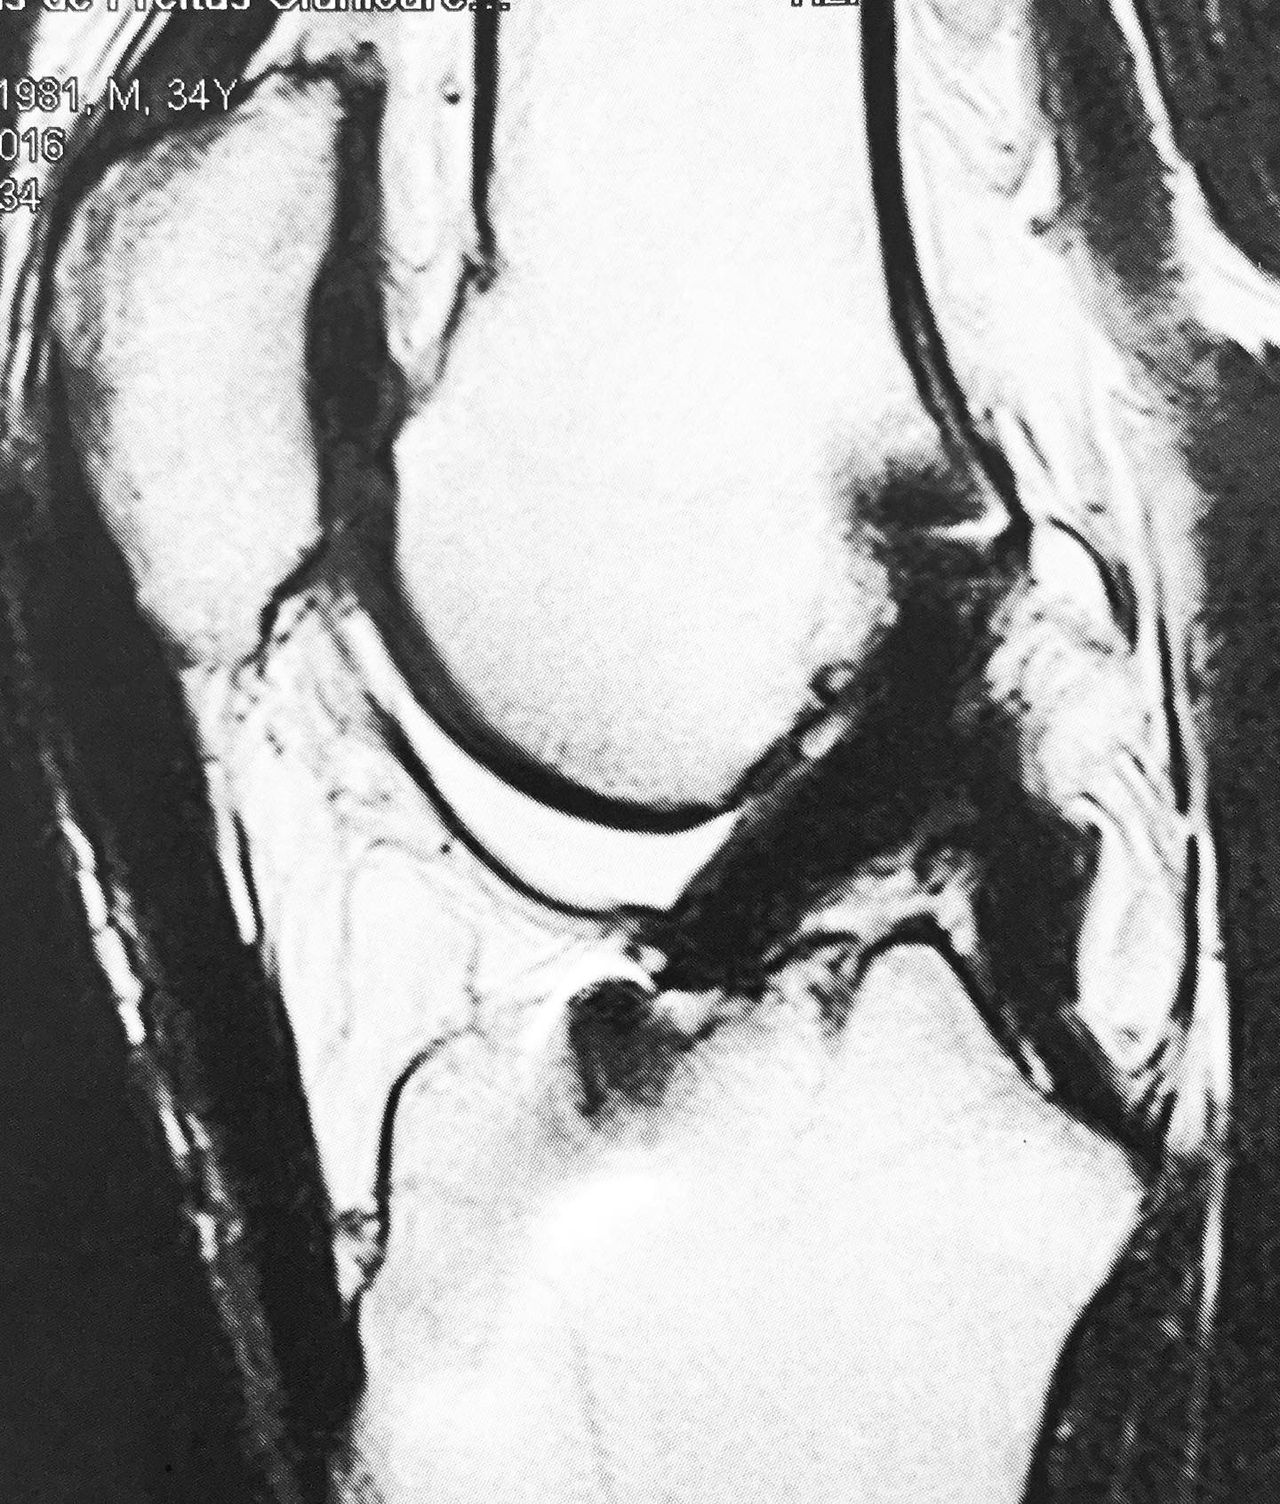

Lesões de ligamentos cruzados do joelho

Quando um paciente sofre entorse do joelho na prática esportiva, sente um deslocamento, com dor e um estalo, e sensação clara de que o joelho saiu do lugar, em geral ocorreu rotura do ligamento cruzado anterior , daí passa a sentir uma insegurança , como se o joelho ficasse solto, às vezes até ao descer do carro. Em geral esta lesão pode ser corrigida com a reconstrução do ligamento cruzado anterior (lca), através de pequenos furos na cirurgia artroscópica e coloca-se um tendão no lugar do lca, fixado com pequenos implantes, recuperando novamente a estabilidade e segurança para praticar esportes, também com o ligamento corrigido, o joelho fica protegido de desgastes futuros .